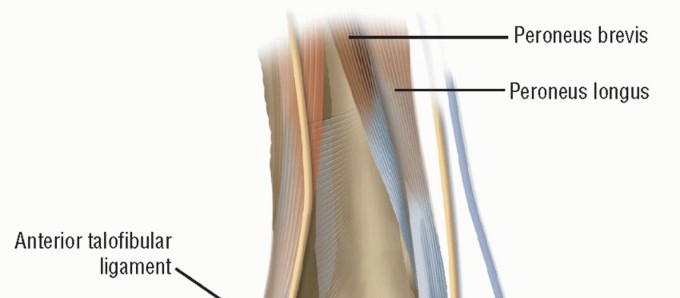

Chronic lateral ankle instability (CLAI) is a debilitating condition frequently encountered in orthopedic practice, typically resulting from recurrent inversion injuries that lead to the attenuation or rupture of the anterior talofibular ligament (ATFL) and the calcaneofibular ligament (CFL). While anatomic repairs, such as the modified Broström-Gould procedure, remain the gold standard for the majority of patients, a distinct subset of the population requires a more robust, non-anatomic reconstruction.

The Watson-Jones procedure, and its subsequent modifications, represents a cornerstone in the surgical armamentarium for non-anatomic lateral ankle reconstruction. By utilizing the peroneus brevis tendon as a tenodesis graft, the modified Watson-Jones technique effectively restricts abnormal anterior talar translation and excessive talar tilt. This comprehensive guide delineates the biomechanical rationale, precise surgical steps, and postoperative protocols required to execute the modified Watson-Jones repair successfully.

The primary objective of the modified Watson-Jones technique is to recreate the stabilizing vectors of the ATFL and, to a lesser extent, the CFL, without relying on attenuated native ligamentous tissue.

In a healthy ankle, the ATFL is the primary restraint to anterior talar translation in plantarflexion, while the CFL restrains inversion in dorsiflexion. The Watson-Jones routing utilizes the peroneus brevis tendon, passing it from the fibula to the talar neck, effectively creating a robust checkrein against anterior subluxation of the talus.

2. Tendon Harvest and Preparation

- Sheath Incision: Open the peroneal sheath as far proximally as the incision allows.

- Tendon Separation: Identify the peroneus brevis and peroneus longus tendons. Sharply separate the peroneus brevis tendon from its muscle belly.

- Fascial Extension: To ensure the transferred tendon is of adequate length for the complex routing, dissect proximally, taking an extension of the muscle fascia along with the tendon.

- Muscle Tenodesis: To preserve the eversion power generated by the proximal peroneus brevis muscle belly, suture the severed distal end of the brevis muscle to the adjacent, intact peroneus longus tendon using non-absorbable braided sutures (e.g., #1 or 0-Vicryl).

- Distal Mobilization: Free the peroneus brevis tendon as far distally as the lateral malleolus.

- Retinaculum Preservation: Crucial Step: Do not disturb or release the superior or inferior peroneal retinaculum. The intact retinaculum acts as a critical pulley, preventing bowstringing of the tendon during active eversion and dorsiflexion.